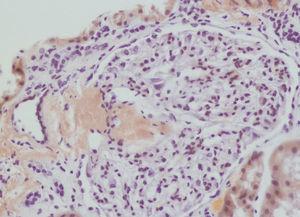

We decided to perform a renal biopsy, which showed that 17 of 26 glomeruli were sclerosed. In some of the non-sclerosed glomeruli, we observed very focal nodular deposits of hyaline eosinophilic, acellular material with weak periodic acid signatures (PAS+), more frequently found in the vascular pole (Figure 1). This material was also observed in greater quantities in arterial and arteriolar walls and interstitium (Figure 2). This material was stained with Congo red stain (Figure 3 and Figure 4), which disappeared after treatment with permanganate, and had birefringence of an apple-green colour with polarised light. Using immunohistochemical techniques, the acellular material showed staining patterns of amyloid A (Figure 5). We also observed interstitial fibrosis and moderate tubular atrophy (20%). With these histological findings, we diagnosed the patient with secondary renal amyloidosis (AA) with glomerular, vascular, and interstitial involvement.

Figure 1. Glomerular amyloid deposits with haematoxylin-eosin stain

Figure 2. Arterial amyloid deposits with haematoxylin-eosin